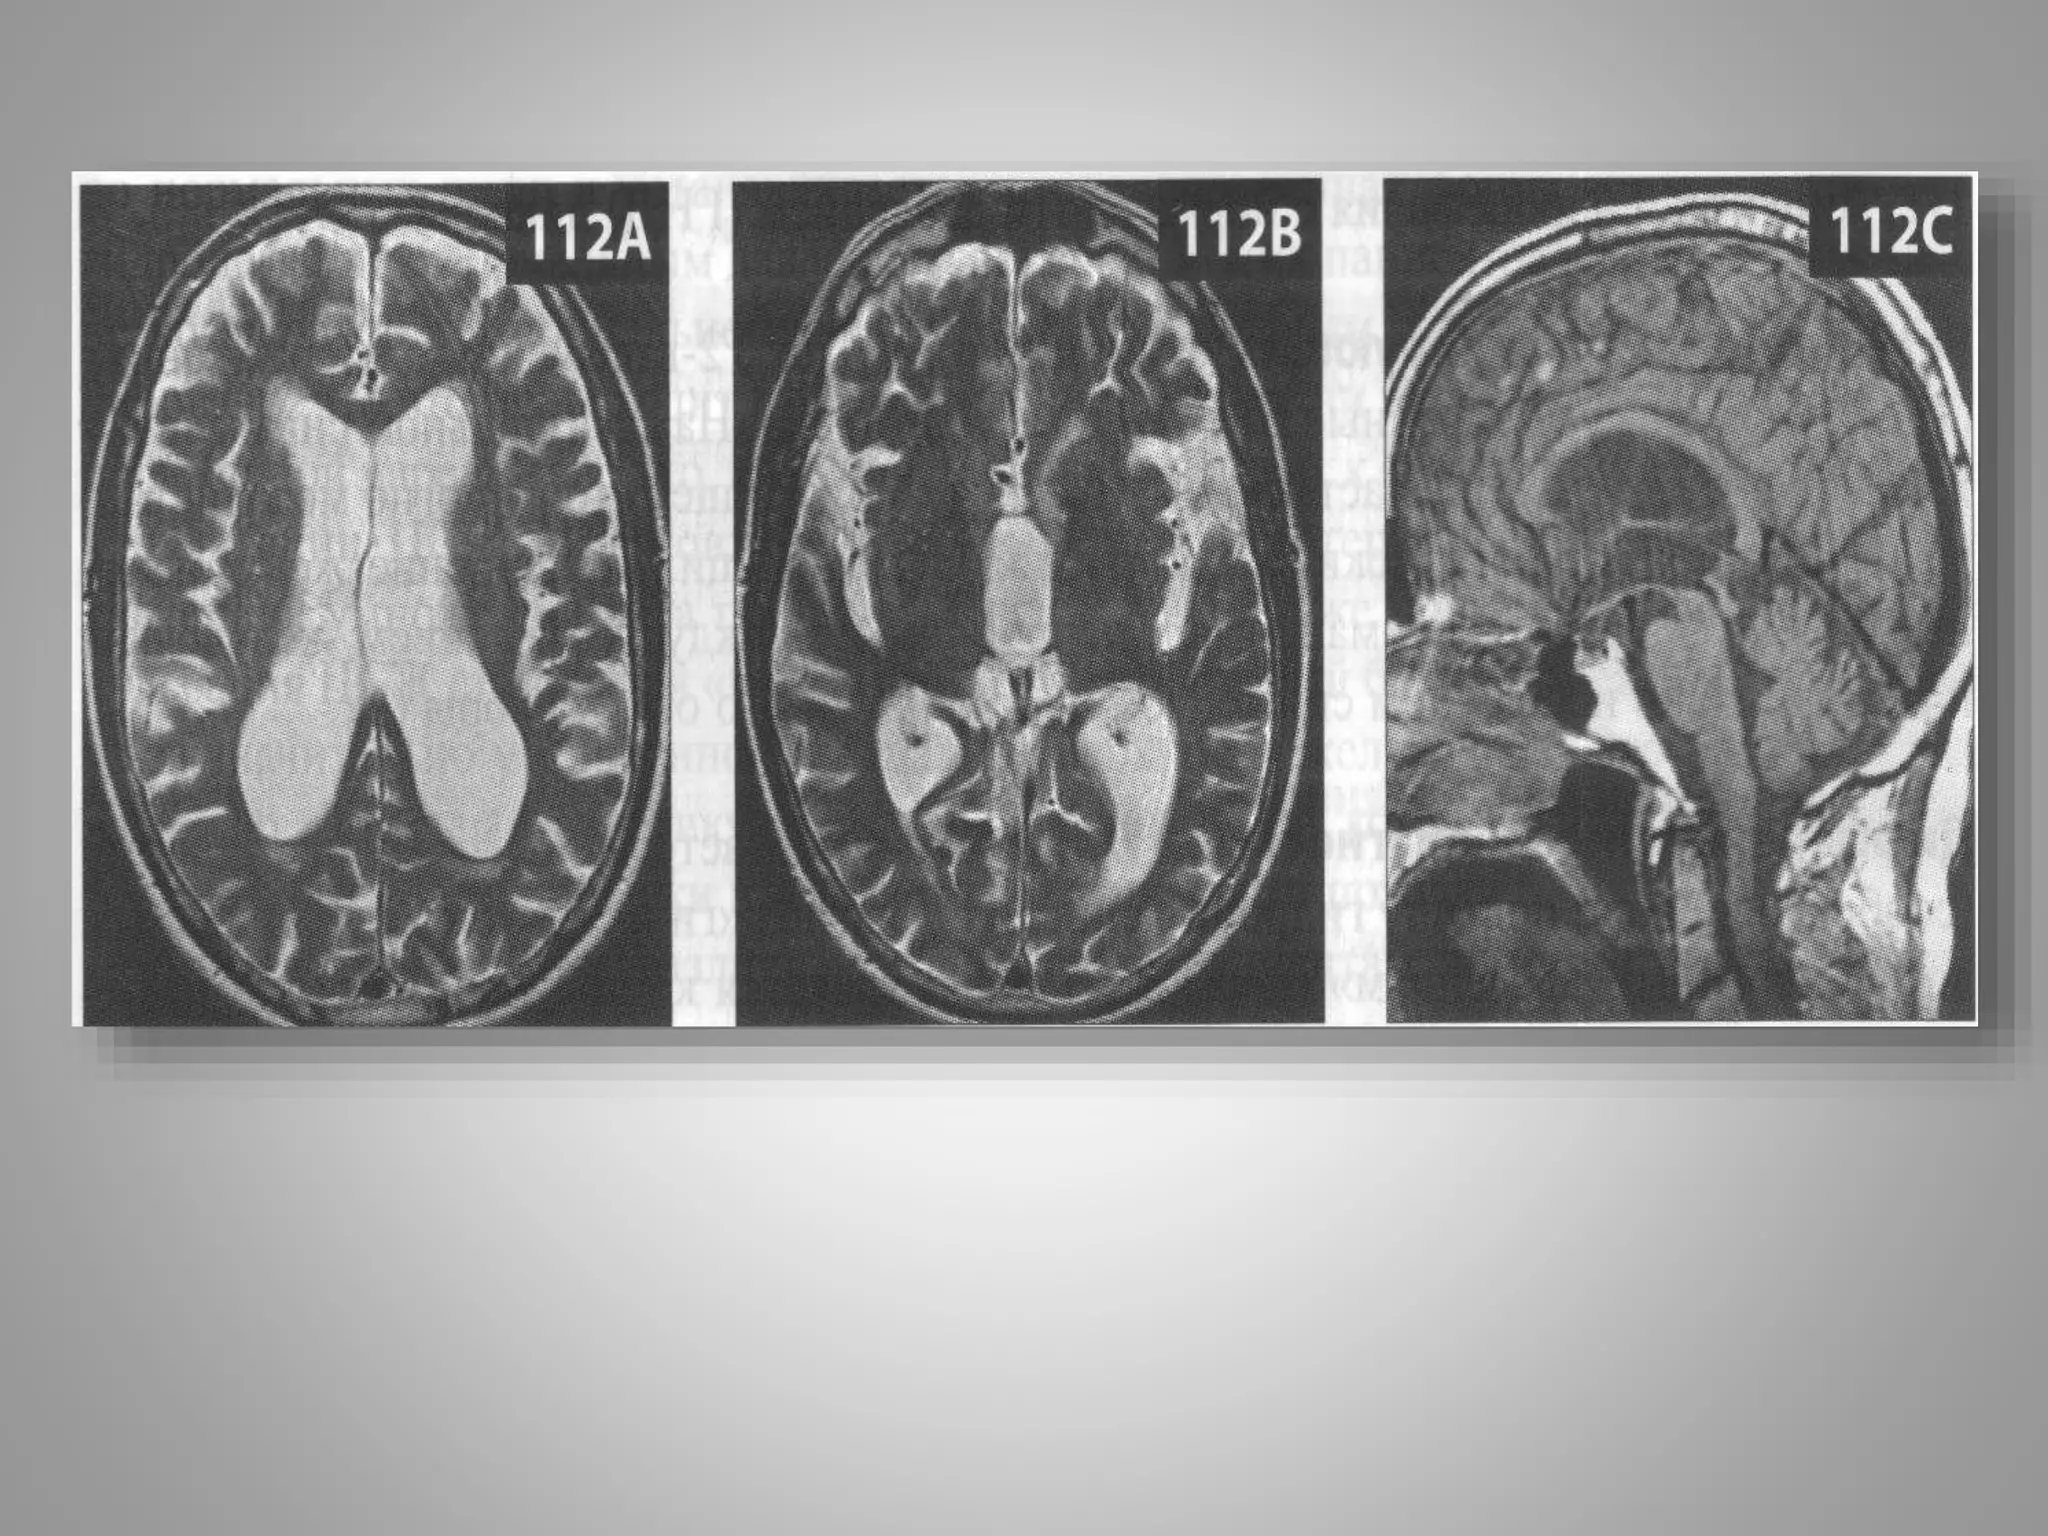

Обстурктивна некомунікативна

гідроцефалія.

• Дитина із скаргами на головний біль вранці.

• Отримані зображення

• Помітне розширення III і бічних шлуночків на Т2-

зважених зображеннях (110 А, В). На сагітальному

знімку в режимі Т1 (110С) видно розтягнутий III

щлуночок і нормальний за розміром IV шлуночок.

• Крім того, є очевидний стеноз або оклюзія сільвієвого

водопроводу.

• В даному випадку причиною

некомунікативної гідроцефалії є стеноз

• Крім того, є очевидний стеноз або оклюзія

сільвієвого водопроводу.